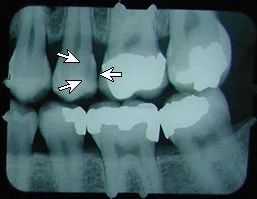

No cavity on first X-ray.

Months later, cavities that start between the teeth can't be seen by visual examination, but they can be detected on an X-ray.

This cavity was detected and filled before the patient felt any discomfort, and before the nerve became infected or the tooth became abscessed.

There is another cavity shown in the X-ray on the right. Can you find it? It's difficult for the untrained eye to spot. Click here to see where it is. (Hint: It's not the left edge of the top left tooth. That's just the edge of the frame around the X-ray).